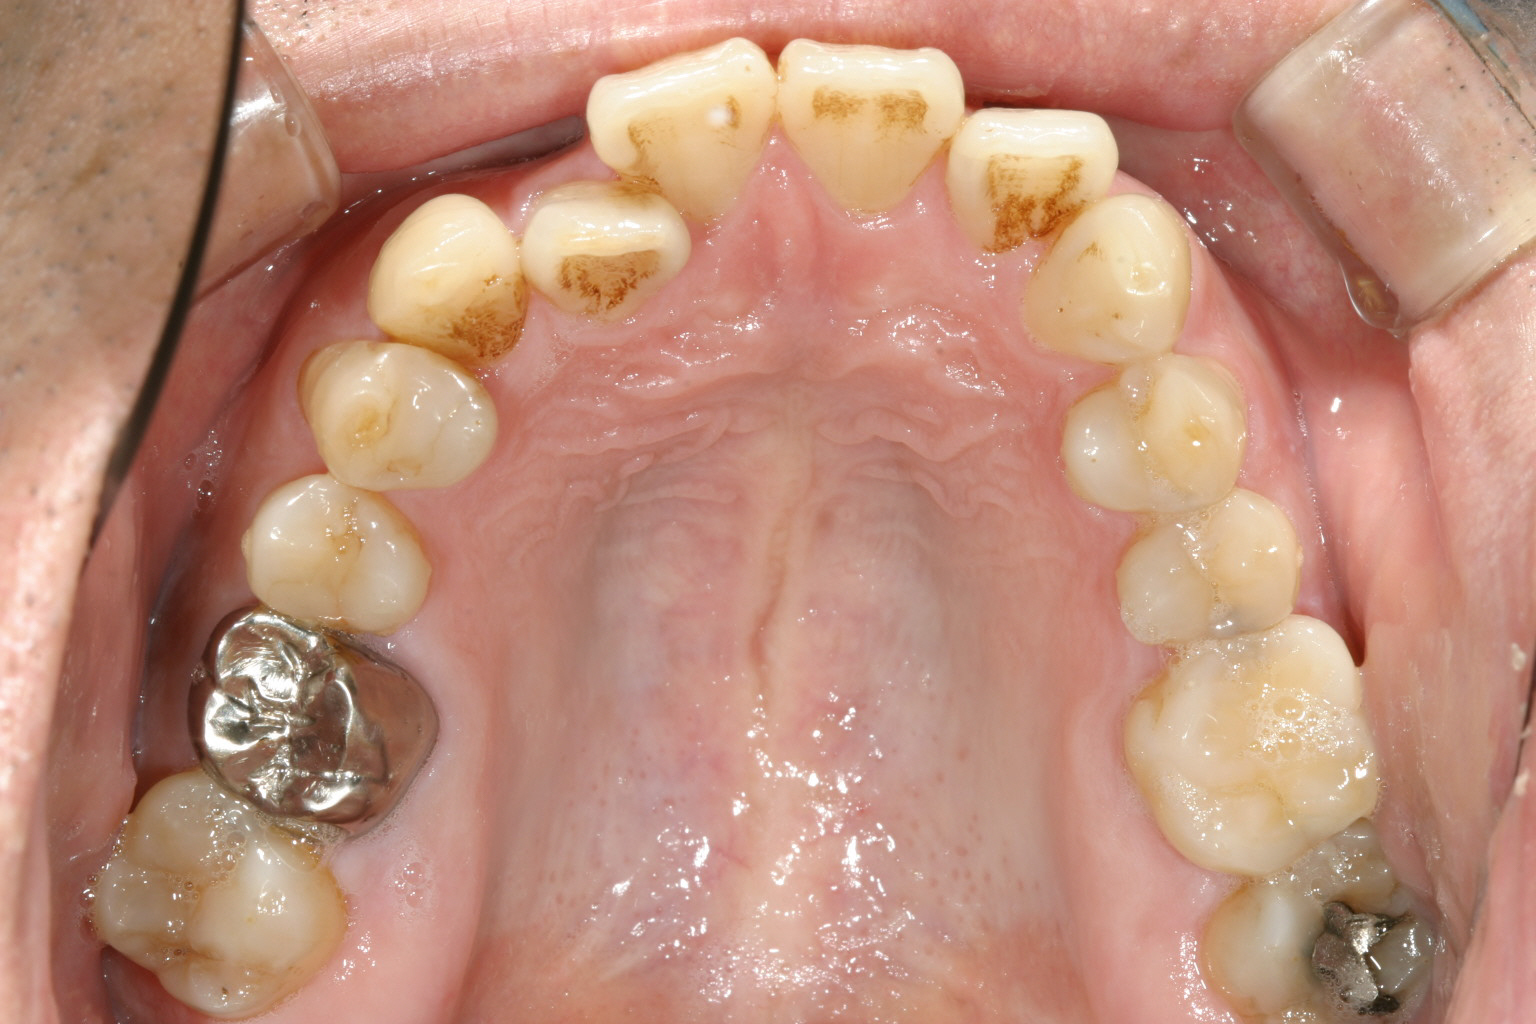

アーチが狭く前歯に叢生が目立ちます。